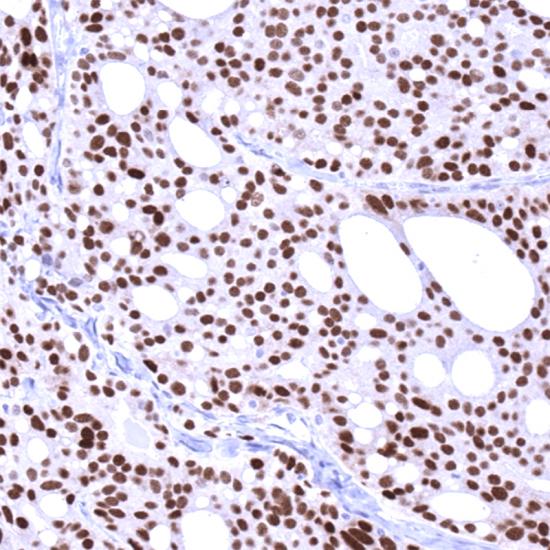

雄激素受體(Androgen Receptor,AR)抗體試劑(免疫組織化學法) 閩廈械備20190054號

• 陽性部位:

細胞核

• 陽性對照:

前列腺癌

雄激素受體的表達與組織分化程度相關,分化好的前列腺腫瘤,雄激素受體比分化差的表達高。在前列腺癌患者中,雄激素受體是一個對激素有反應性的標志物。